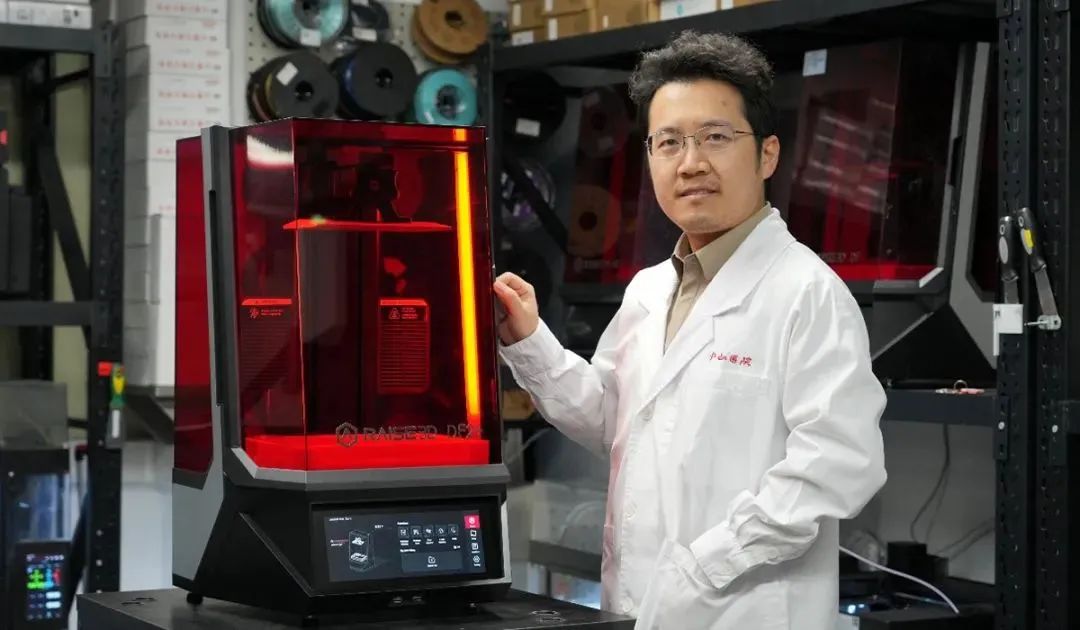

基于这些优势,于博士联系了Raise3D,并了解到Raise3D正在研发一款全新的DLP 3D打印机——Raise3D DF2。这是一台在国内完成研发生产的设备,具备稳定的性能,支持多种树脂材料。

同时,Raise3D团队具有优秀的打印服务能力,能够对客户需求进行快速的响应与评估,为用户提供最适配的解决方案。各方一拍即合,决定采用DF2,进行前鼻孔支撑模的原型设计与验证。

Raise3D DF2 3D打印机

复旦大学附属中山医院耳鼻喉科团队于浩然博士与Raise3D DF2+ 3D打印机合影